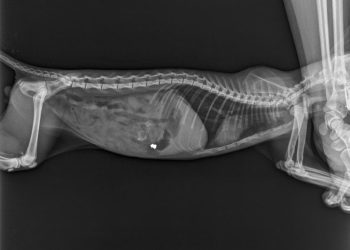

Ντροπή και αποτροπιασμό προκαλούν τα όσα εκτυλίχθηκαν στην Αλεξανδρούπολη. Ένα μικρό γατάκι που έμενε στην Αλεξανδρούπολη, μεταφέρθηκε στον κτηνίατρο, επειδή ...